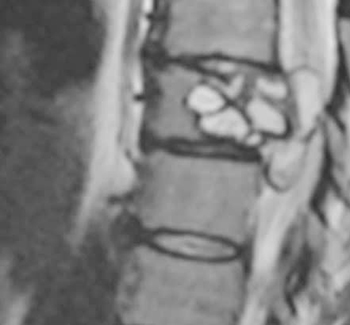

A few years ago, a woman in her mid-20s suddenly found herself unable to walk. She'd stand up, only for her muscles to give out and drop her to the floor. She was also doubled over in pain, suffering an electric sensation running through her back. She eventually visited her local hospital, and one MRI later, she had a diagnosis. Her spine was infected with tapeworm larvae.

As far as anyone call tell, the patient (somehow) accidentally ingested the egg of a tapeworm species that usually only infects dogs and farmyard animals, whereupon it rode her bloodstream like a red river rapids ride until it eventually lodged in her vertebrae. There, the egg hatched and developed into a cyst. The muscular weakness? The electrical shocks? Those were all caused by the cyst and its tapeworm occupants bumping and wiggling and hacking their way to her central nervous system, which ran clear through that vertebrae.